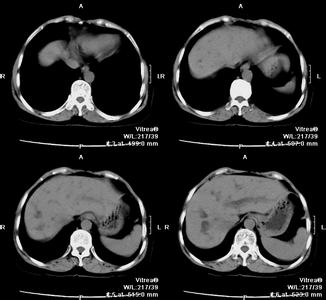

某些患者可有短期梗阻性黄疸表现,大便呈陶土色,肝功能多有明显损害。黄疸达顶峰并开始消退前消化道症状表现改善。如出现淤胆型肝炎者此期可见酶、胆分离现象。约为2~6周。主要表现为黄疸出现和加深。先有尿色变深黄,继见巩膜及皮肤黄染,黄疸加深在1~2周内达高峰。此时多数不再发热,但消化道症状和乏力明显加重,大便色泽变浅,肝肿大并有叩痛,皮肤瘙痒和心动徐缓。